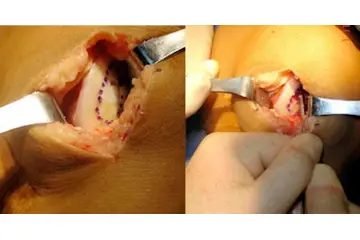

Fibröz kıkırdak, travma veya aşınma sonucu zarar görebilir. Bu tür durumlarda, kıkırdak onarım süreçleri yavaş ilerleyebilir ve genellikle cerrahi müdahale gerektirebilir. Fibröz Kıkırdak Hastalıkları Fibröz kıkırdak ile ilişkili bazı hastalıklar ve durumlar şunlardır:

Fibröz kıkırdağın iyileşme kapasitesinin düşük olması, yaralanma durumlarında ciddi sorunlar doğurabilir. Bu tür kıkırdak, kan damarları ve sinirlerden yoksun olduğu için, yaralanma sonrası vücudun onarım mekanizmaları devreye giremez. Sonuç olarak, hasar gören fibröz kıkırdak tam olarak iyileşmeyebilir ve bu da uzun vadede omurga sağlığını etkileyerek ağrı, hareket kısıtlılığı ve diğer ortopedik sorunlara yol açabilir.